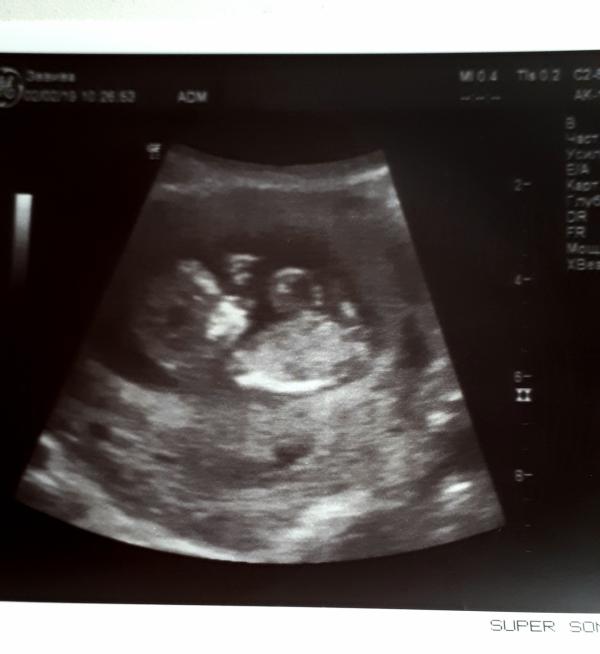

12 недель ❤